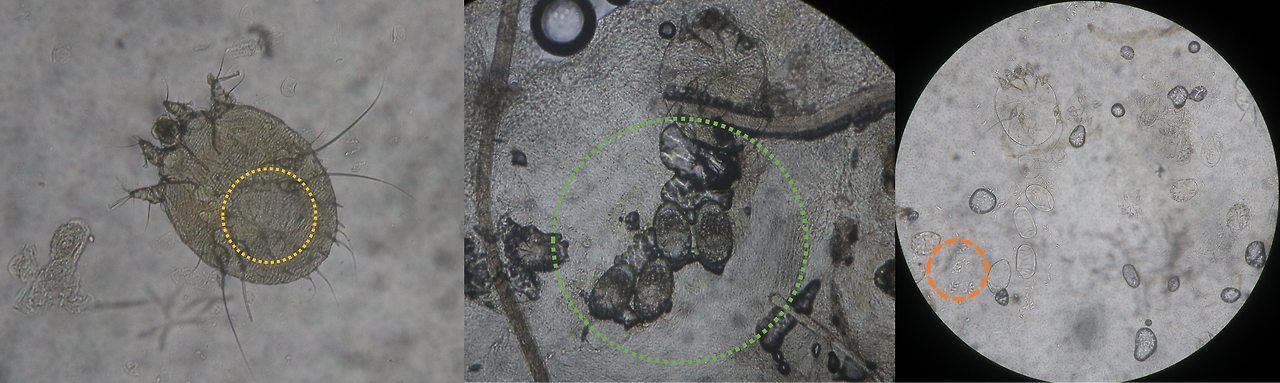

왼쪽: 옴 암컷, 알을 품고 있다. 가운데: 굴을 파고 알을 낳는 모습, 맨 오른쪽: 주황색 동그라미 안의 작은 알갱이가 옴의 배설물이다.

옴은 왼쪽처럼 동그란 로봇청소기같이 생겼고 크기는 0.2-0.4mm 정도 되는 진드기 목의 곤충이다.

보통 병변 부위의 각질층을 칼로 긁어서 현미경을 통해 옴의 성체, 유충, 알, 배설물 중 한 개라도 보이면 확진이 가능하다. 더모스콥이라는 피부확대경으로 특징적인 옴 병변을 보는 방법도 있지만, 가장 확실하게 현미경으로 확인하는 것을 더 추천한다.